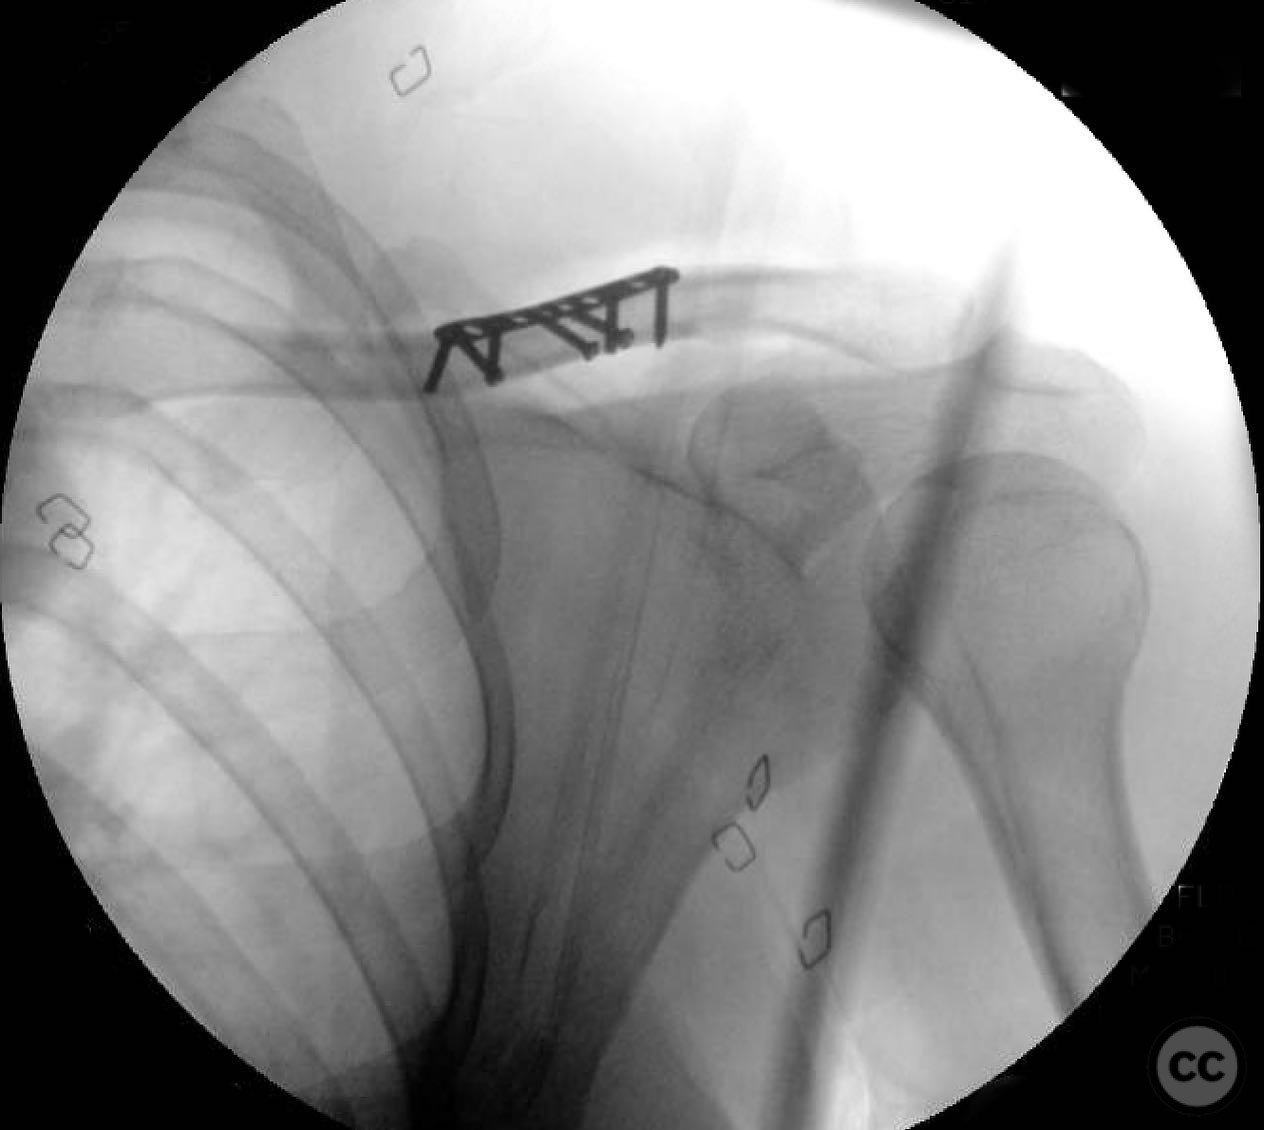

During the procedure, anatomic reduction of the butterfly fragments was achieved using 2.4mm lag screws for interfragmentary compression. The main segment reduction proved challenging due to instability; hence, a 2.4mm "clamp replacement plate" was temporarily used to maintain reduction. A reconstruction plate was contoured and applied to the anterior inferior clavicle, providing a neutralization construct. Absolute stability was achieved, anticipating primary bone healing.